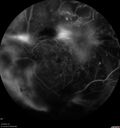

Macular ischemia left eye in type I diabetic (enlarged foveal avascular zone)213 views29 year old female with type I diabetes since age 5. Left eye has enlarged FAZ with vision of 20/20 OD and 20/60 OS. Both eyes have CSME. The left eye did have focal laserApr 12, 2023

Macular ischemia left eye in type I diabetic (enlarged foveal avascular zone)229 views29 year old female with type I diabetes since age 5. Left eye has enlarged FAZ with vision of 20/20 OD and 20/60 OS. Both eyes have CSME. The left eye did have focal laserApr 12, 2023

Macular ischemia left eye in type I diabetic (enlarged foveal avascular zone)216 views29 year old female with type I diabetes since age 5. Left eye has enlarged FAZ with vision of 20/20 OD and 20/60 OS. Both eyes have CSME. The left eye did have focal laserApr 12, 2023